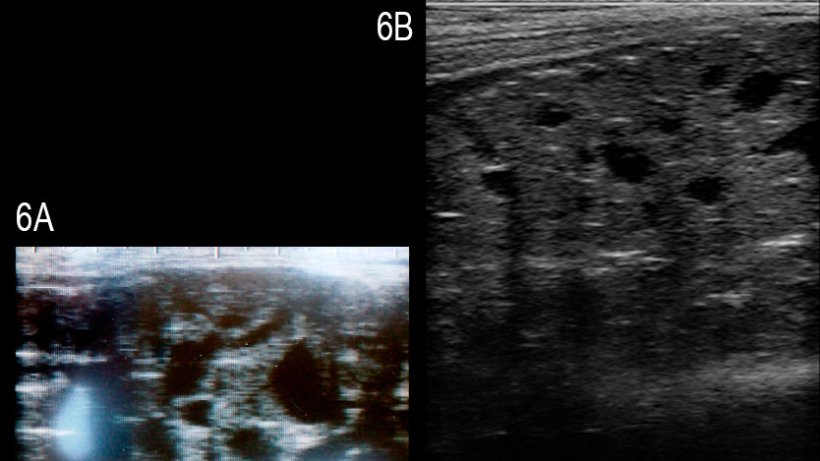

Os estudos sobre o uso prático da ecografia na reprodução do varrascos são escassos. O diâmetro dos testículos tem-se determinado com a finalidade de o relacionar com o número total de espermatozóides produzidos, em média, no ejaculado (Clark et al., 2003) ou para avaliar o desenvolvimento puberal (Ford & Wise, 2010). Se bem que a correlação do diâmetro de ambos testiculos e o número total de espermatozóides foi pobre, pelo menos nos varrascos com mais de 8 meses; a determinação do tamanho testicular dos varrascos mais jovens, aproximadamente aos 4 meses, pareceu útil para a previsão do volume testicular e de produção de esperma quando o varrasco chegava à maturidade. Há um relatório recente sobre um varrasco Large White infértil com uma degeneração multiquística da glândula bulbouretral; na glândula afectada visualizaram-se quistos anecogénicos sólidos e bem definidos de diferentes tamanhos (figura 6, Grahofer et al., 2016).